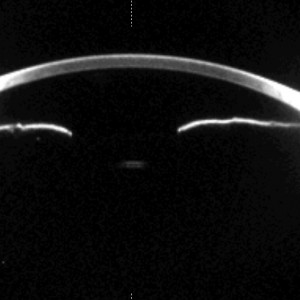

Plateauiris

Plateau-IrisPlateauiris-Konfiguration